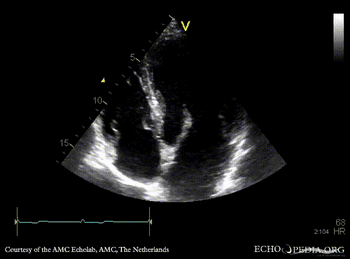

| Marfan Syndrome

| Courtesy of: AMC Echolab, AMC, The Netherlands

| A4CH

A2CH